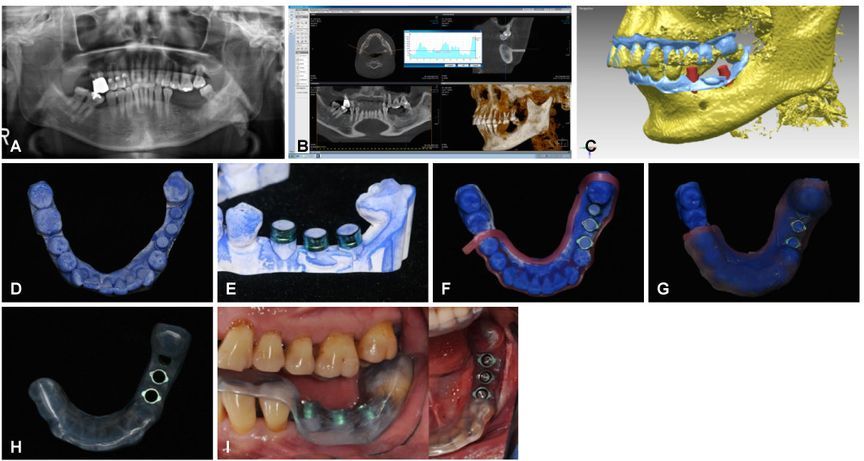

Применяют новые 3D-технологии также в стоматологии и челюстно-лицевой хирургии. Они позволяют с удивительной точностью планировать и проводить лечение, а также проектировать и создавать индивидуальные протезы и временные коронки как отдельных зубов, так и целых челюстных фрагментов.

Как это происходит:

1. Совмещается 3D-скан челюсти пациента с данными компьютерной томографии для высокоточного планирования размещения имплантата, с учетом качества кости пациента, расположения нерва и артерии.

2. Определяется размер и форма имплантата и требуемый угол его установки.

3. По этим данным, на 3d-принтере печатается хирургический шаблон, позволяющий недопустить врачебную ошибку при установке имплантата во время операции.

4. Печатается или фрезеруется временная коронка, для правильного заживления мягких тканей на послеоперационный период.

5. Печатается или фрезеруется постоянная металлокерамическая коронка из биосовместимого металла (титан или кобальт-хром).